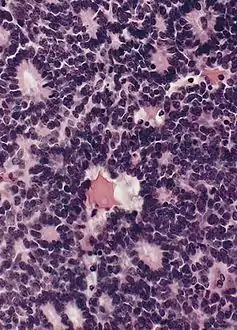

Morphology

Gross and microscopic appearances of retinoblastoma are identical in both hereditary and sporadic types. Macroscopically, viable tumor cells are found near blood vessels, while zones of necrosis are found in relatively avascular areas. Microscopically, both undifferentiated and differentiated elements may be present. Undifferentiated elements appear as collections of small, round cells with hyperchromatic nuclei; differentiated elements include Flexner-Wintersteiner rosettes, Homer Wright rosettes,[29] and fleurettes from photoreceptor differentiation.[30]

Large exophytic white tumor with foci of calcification producing total exudative retinal detachment Flexner-Wintersteiner rosettes in retinoblastoma

Flexner-Wintersteiner rosettes in retinoblastoma- Retinoblastoma, 400 X magnification